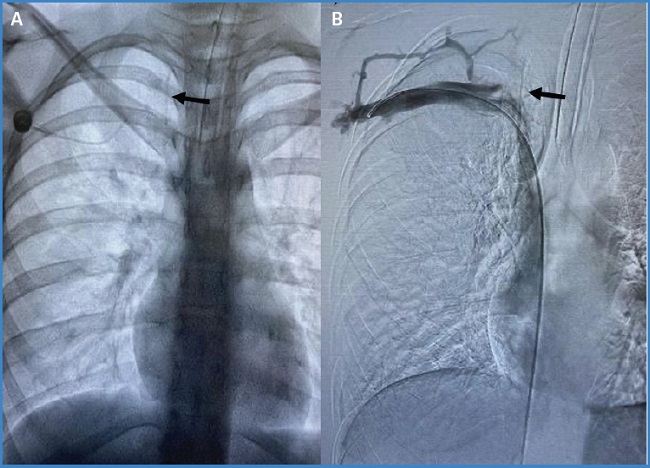

En marzo de 2024 fue llevada nuevamente al quirófano. Se le realizó una incisión sobre la cicatriz previa, con evidencia de fibrosis en todo su trayecto, hasta la exposición del reservorio con un radioscopio, con evidencia de catéter fracturado (Fig. 1A). Se retiró el catéter proximal y se observó un segmento distal en el confluente yugulosubclavio y vena cava superior, dentro del trombo venoso a este nivel anatómico (Fig. 1B).

Figura 1. A. Radiografía anteroposterior. La flecha negra muestra el segmento fracturado del catéter. B. Flebografía por fluoroscopia en la que se observa (flecha negra) el segmento del catéter en confluente yugulosubclavio y vena cava superior intratrombo.